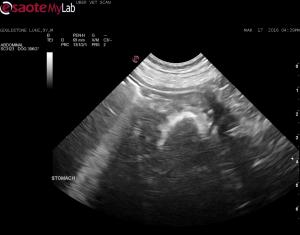

– u/s suspicious for a gastric FB and gastritis pattern; reactive jejnual LN’s – rest of scan normal

Am I crazy, or does this look like a gastric FB? I was really expecting to find something like a splenic mass in this patient, so was kind of surprised with the stomach lesion but history would fit with a chronic gastric FB. The pet has not been on oral meds.

Its about <2 cm so be sure

Its about <2 cm so be sure this isnt a dissolving sucralfate or something… I would certainly rescan before gastrotomy or scope